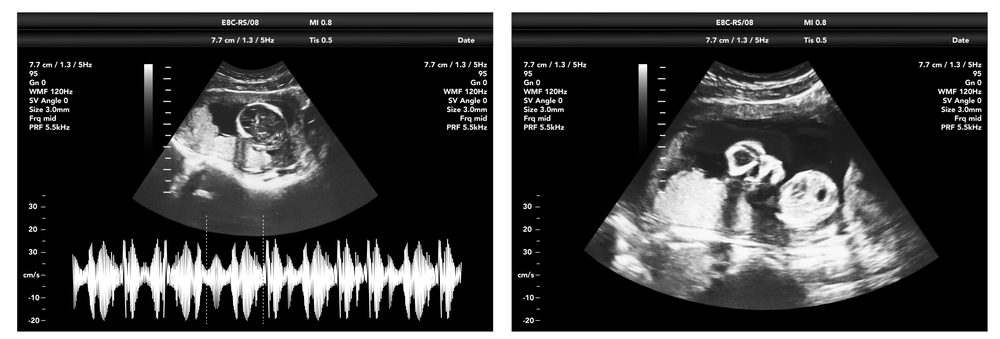

Our X-ray service is available Monday to Friday from 8:00 AM to 8:00 PM, providing radiographic examinations for the assessment of bone injuries, chest conditions, and other internal structures. Our Ultrasound Scan service operates Monday to Friday from 8:00 AM to 4:00 PM, offering safe and non-invasive imaging for the evaluation of abdominal organs, soft tissues, pregnancy, and other medical conditions.